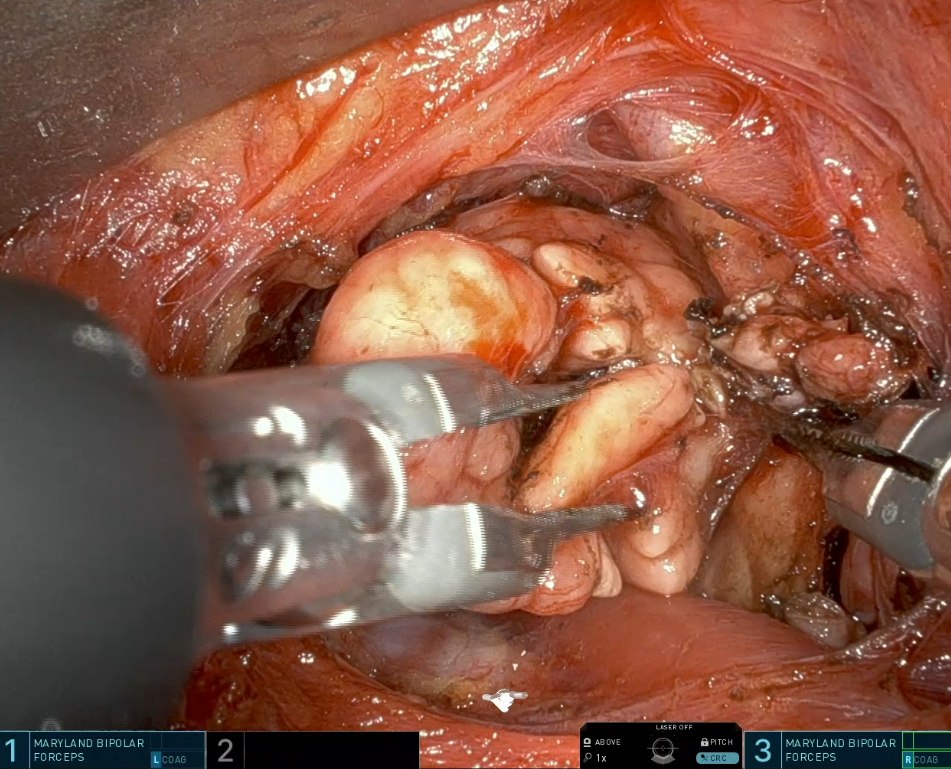

10대 젊은 남자 환자의 악하선 제거에 활용한 사진입니다. 악하선까지는 내시경이나 로봇을 쓰지 않더라도 제거가 어느정도 용이합니다. 종양이 절개선으로 부터 가장 먼쪽 – 인체 중앙 – 을 향하고 있지 않다면 ‘반드시’ 로봇 수술이 필요한 것은 아닙니다.

적용 사례 4. 로봇 갑상선 수술 / 로봇 침샘(악하선 수술)

이하선은 절개선 바로 가까이 위치하여 로봇을 쓸 필요가 별로 없습니다만, 악하선은 상황에 따라 로봇 또는 내시경이 의미있게 사용됩니다. 그리고 갑상선도 귀뒤 접근을 통해 가능합니다. 추후 포스팅 예정으로 최근에는 개인적 선호로 로봇 갑상선 수술은 겨드랑이를 통한 접근을 주로 하고 있습니다.

악하선 수술은 위에서 언급했듯이 반드시 로봇을 쓸 이유가 없어서 환자분들께 먼저 권하지는 않습니다만, 비용/수술 시점 등의 이유로, 또 타기관에서 로봇수술에 대해 설명을 미리 듣고와서 먼저 선택하시는 분들도 계십니다.